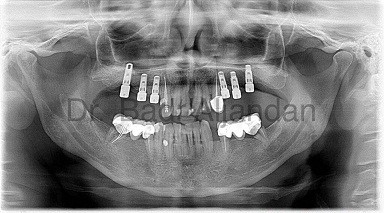

The implants themselves are tiny titanium posts, which are inserted into the jawbone where teeth are missing. These metal anchors act as tooth root substitutes. They are surgically placed into the jawbone. The bone bonds with the titanium, creating a strong foundation for artificial teeth. Small posts are then attached to the implant, which protrude through the gums. These posts provide stable anchors for artificial replacement teeth.

For most patients, the placement of dental implants involves two surgical procedures. First, implants are placed within your jawbone. For the first three to six months following surgery, the implants are beneath the surface of the gums gradually bonding with the jawbone. You should be able to wear temporary dentures and eat a soft diet during this time. At the same time, your dentist is forming new replacement teeth.

After the implant has bonded to the jawbone, the second phase begins. Dr. Al-jandan will uncover the implants and attach small posts that protrude through the gums and will act as anchors for the artificial teeth. When the artificial teeth are placed, these posts will not be seen. The entire procedure usually takes six to eight months. Most patients experience minimal disruption in their daily life.

Using the most recent advances in dental implant technology, Dr.Al-jandan is able to place single stage implants. These implants do not require a second procedure to uncover them, but do require a minimum of six weeks of healing time before artificial teeth are placed. There are even situations where the implants can be placed at the same time as a tooth extraction – further minimizing the number of surgical procedures.

Dental Implant placement is a team effort between an oral and maxillofacial surgeon and a restorative dentist. While Dr. Al-jandan performs the actual implant surgery, initial tooth extractions, and bone grafting if necessary, the restorative dentist (your dentist) fits and makes the permanent prosthesis. Your dentist will also make any temporary prosthesis needed during the implant process.